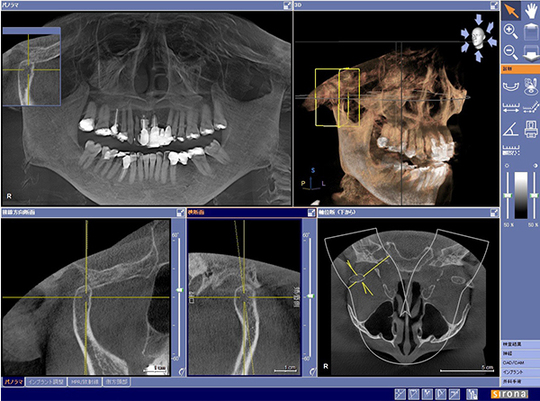

お口の中を14箇所に細かく分けてレントゲンを撮影します。レントゲンでは目視や写真では確認できない歯の中の状態と骨の状態も調べることができます。